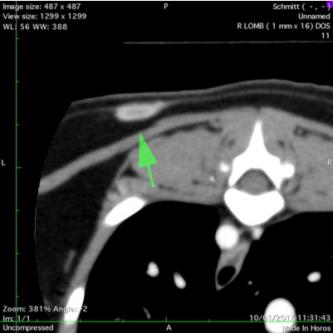

Les scanners thoraciques:

Cet examen est très utile en complément d'une radiographie. Il permet aussi de visualiser des lésions là l'echographie ne peut rien faire, comme par exemple  une recherche de lésion intra-pulmonaire.

L'examen va permet d'une part d'apprecier la structure interne de la lésion (et d'en determiner la nature) et d'autre part de la délimiter précisément en vue d'une chirurgie thoracique.

Scanners thoraciques anormaux